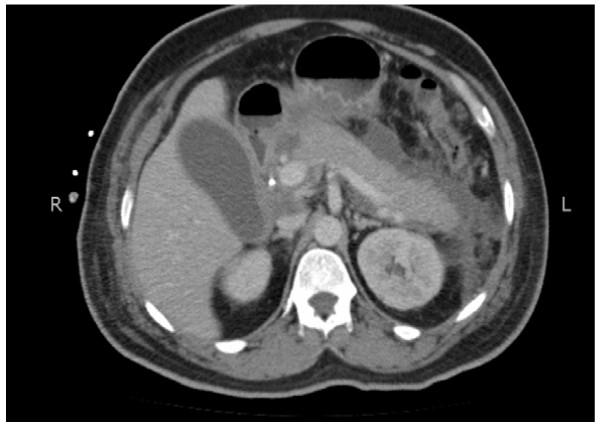

We present the case of a 44-year-old Asian man with Mirizzi's syndrome who was initially diagnosed as having cholangiocarcinoma based on his clinical presentation, raised cancer antigen 19-9 levels and radiological findings. Our patient was diagnosed as having Mirizzi's syndrome intra-operatively and subsequently a cholecystectomy was performed with restoration of biliary drainage. Careful clinical assessment during surgery with the help of intra-operative frozen section helped in establishing the definitive diagnosis and altered the surgical procedure for our patient.

我们报告一例44岁亚洲男性Mirizzi综合征病例,该患者最初根据临床表现、癌胚抗原19-9水平升高及影像学检查结果被诊断为胆管癌。我们的患者在术中被诊断为Mirizzi综合征,随后进行了胆囊切除术并恢复了胆汁引流。术中借助冰冻切片进行仔细的临床评估有助于明确诊断,并改变了我们患者的手术方式。